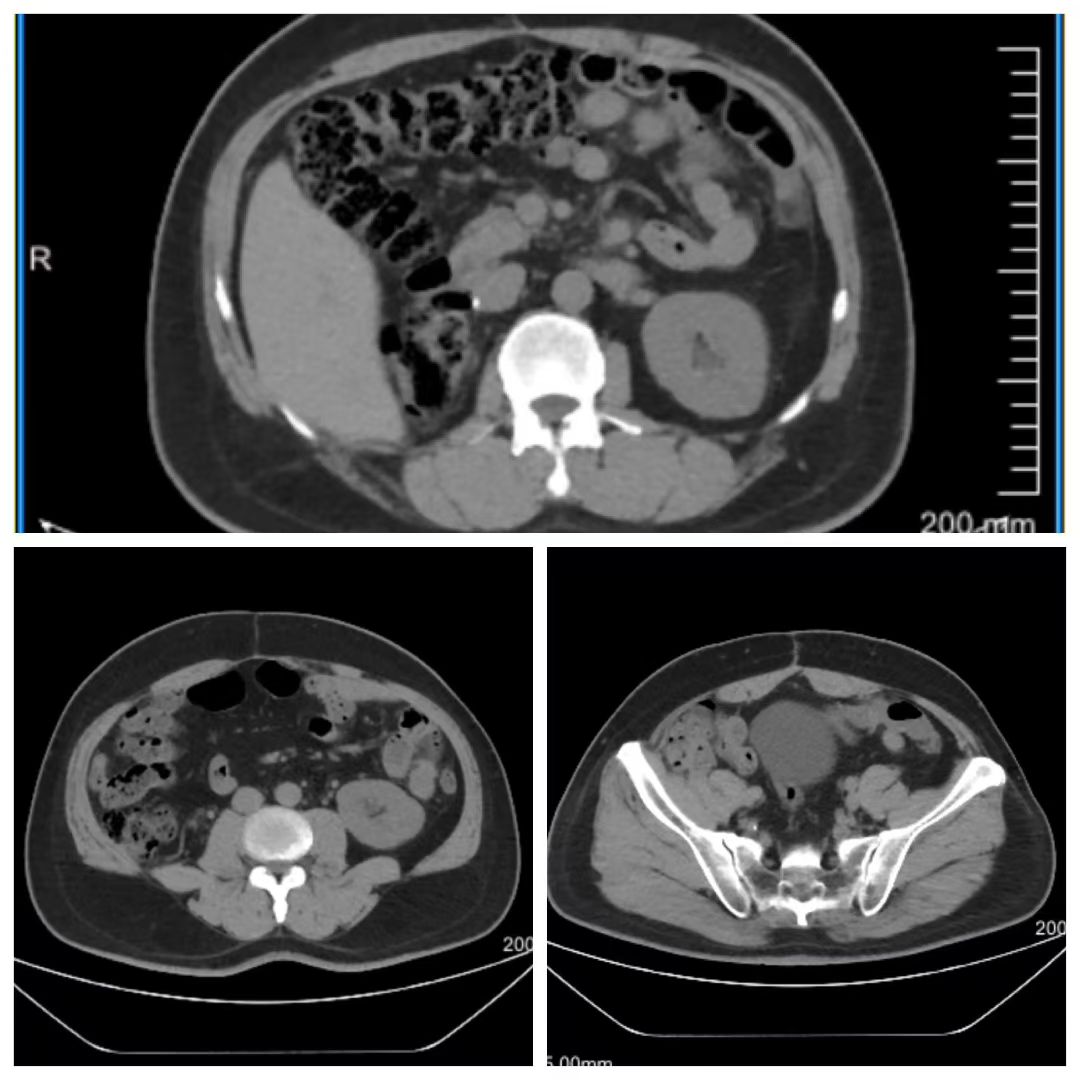

术后半年复查腹部CT未见复发